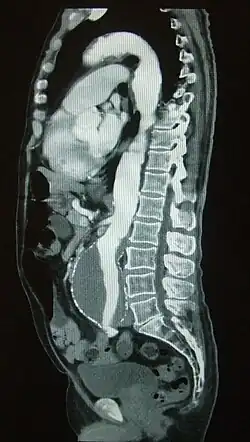

Die CT-Angiographie (computertomographische Angiographie, CTA) ist ein bildgebendes Verfahren in der Medizin, mit dessen Hilfe Blutgefäße im Körper dargestellt werden können. Die Untersuchung bedient sich der modernen Mehrzeilen-Computertomographie. Aus den computertomographischen Schichtbildern werden mithilfe schneller Computer die Arterien oder Venen segmentiert und in frei rotierbaren 3D-Darstellungen ausgegeben. Moderne sogenannte volume renderings werden oft eingefärbt (die Rohbilder sind immer schwarz-weiß). Die darstellbaren Gefäße sind hierbei z. B. die Arterien und Venen in Gehirn, Lunge, Leber, Milz, Nieren und die Gefäße in den Extremitäten. Schnelle Scanner können auch Angiographiebilder der Kranzgefäße am schlagenden Herz erzeugen.